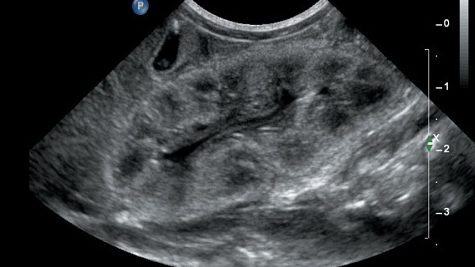

Trong y học, echo thận hay còn gọi là siêu âm thận, là một kỹ thuật chẩn đoán hình ảnh không xâm lấn, sử dụng sóng siêu âm tần số lớn để xây dựng những hình ảnh chân thật về cấu trúc, kích thước, dấu hiệu điển hình của các bệnh lý về thận. Đặc biệt, siêu âm thận có giá trị cao trong việc phát hiện các bệnh lý khu trú ở thận như sỏi thận, nang thận, áp xe thận hay thận ứ nước.

Điểm mạnh của kỹ thuật siêu âm thận đó là phát hiện những bất thường. Thông qua hình ảnh siêu âm, bác sĩ có thể nhận thấy những bệnh lý thận lan toả hoặc khu trú. Những đặc điểm cho phép phát hiện các bệnh lý bao gồm:

Thận ứ nước: Tình trạng này sẽ được đánh giá thông qua sự tổn thương giữa bể thận, đài thận và niệu quản được thể hiện trên hình ảnh siêu âm.

Sỏi thận: Thể hiện trên kết quả siêu âm đó là hình ảnh bóng tăng âm có hình vòng, nguyên nhân có thể do thận bị ứ nước do có sỏi ở niệu quản. Tình trạng này thường gặp ở những bệnh lý như sỏi ở bể thận, đài thận, nốt vôi hoá ở nhu mô thận hoặc sỏi san hô…

Abces thận hoặc quanh thận: Thường thấy khối hỗn hợp trong có hoá dịch, không đồng nhất, giới hạn không rõ ràng.

Máu tụ quanh thận: Trong hình ảnh siêu âm có lớp trống hình liềm ở vùng dưới bao thận có thể làm cho thận bị lệch vị trí, nguyên nhân thường là do chấn thương.

U thận: Thông qua hình ảnh siêu âm có thể xác định đây là u thận nhưng không biết được là u lành hay u ác tính.